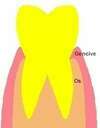

Dans certains cas, une dent peut être cariée ou fracturée sous la gencive, voire même plus bas que le niveau osseux. Une partie de la dent est cachée. L’élongation coronaire est une intervention chirurgicale qui permet d’augmenter la partie visible de la dent. Cette dent sera ainsi accessible pour être restaurée par une couronne.

Dans certains cas, une dent peut être cariée ou fracturée sous la gencive, voire même plus bas que le niveau osseux. Une partie de la dent est "cachée ".

L’élongation coronaire est une intervention chirurgicale qui permet d’augmenter la partie visible de la dent.

La dent a été nettoyée de sa carie et les parties fragiles ont été supprimées. Il faudra supprimer l'os et la gencive au dessus des traits noirs.

L’élongation coronaire est un repositionnement chirurgical de la gencive et une retouche du contour osseux.